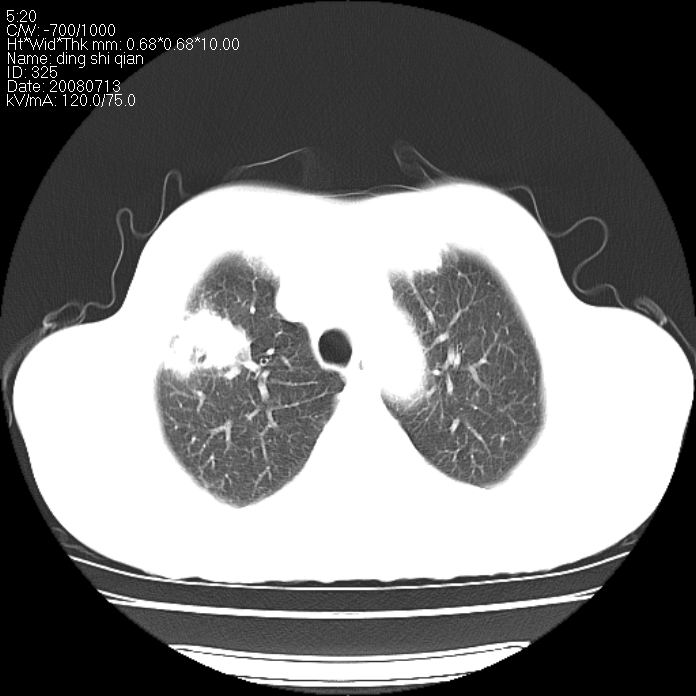

标题: CT14654:男 50岁 近来胸痛 [打印本页]

标题: CT14654:男 50岁 近来胸痛

右侧上肺块状软组织影,浅分叶,边缘毛刺证,与胸膜粘连,考虑:周围性肺癌

右肺上叶周围型肺癌可能性大。

右侧上肺块状软组织影,浅分叶,边缘毛刺证,与胸膜粘连,考虑:周围性肺癌!支持!

典型右肺周围型肺癌

右肺上叶周围型肺癌。